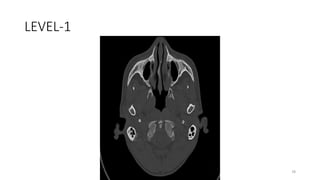

LEVEL-1